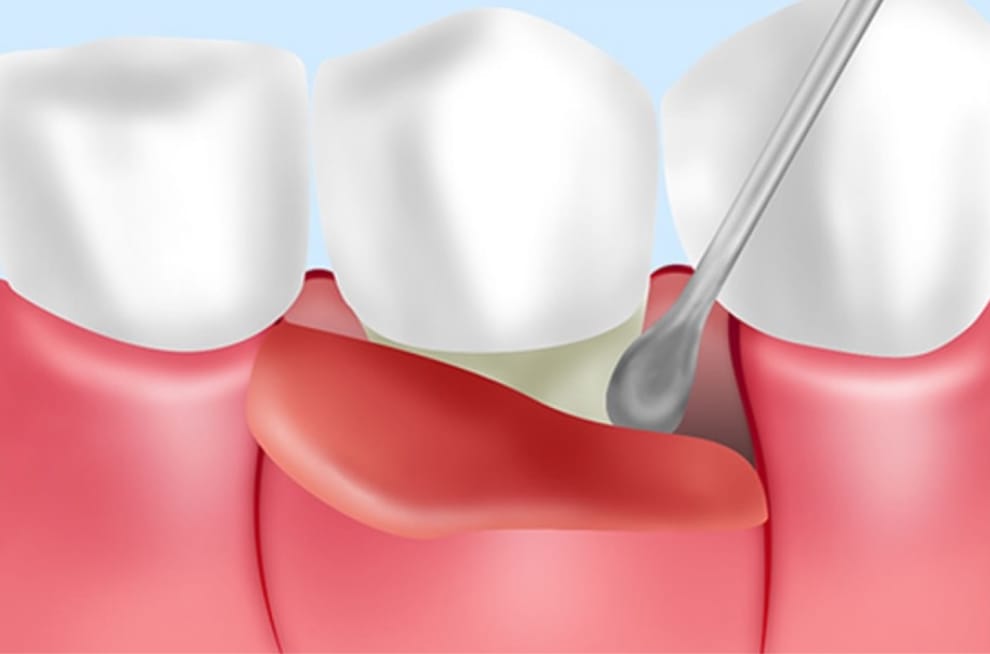

歯周ポケットの有無や深さの測定をはじめ、歯の動揺度やプラークの付着量などから、歯周病の進行度を確認します。

②2つのスケーラーを駆使した歯石除去

歯周病予防・改善のため、スケーラーという専門器具を用いて歯面や歯間に付着した歯石を取り除きます。大井町フラミンゴ歯科では「超音波スケーラー」と「ハンドスケーラー」の2つを駆使して、隅々まで徹底した処置を行なっています。

ハンドスケーラーは、歯の間や細かい部分に付着した歯垢・歯石の除去に適しています。超音波スケーラーと併用することで、取りこぼしのない徹底した歯石の除去が可能となります。

マイクロスコープを用いての精密な歯石除去

肉眼の最大80倍まで視野を拡大し、歯間や歯周ポケット内を目でしっかりと確認することにより、取りこぼしのない的確な処置が可能となります。

歯周外科治療による症状の改善

麻酔後に歯茎を切開し、歯周ポケット内部を露出した状態で歯石の除去と感染歯肉の切除を行います。外科処置ですので、負担は大きくなりますが必要な場合にはご提案いたします。